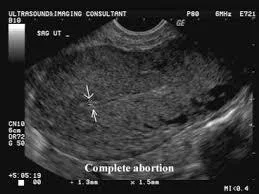

Complete miscarriage

- Clinical feature:

- Expulsion of all products of conception.

- Cessation of bleeding and abdominal pain.

- on examination:

- P.V.: closed cervix.

- Investigations:

- US: empty uterus.

- Treatment:

- Supportive.